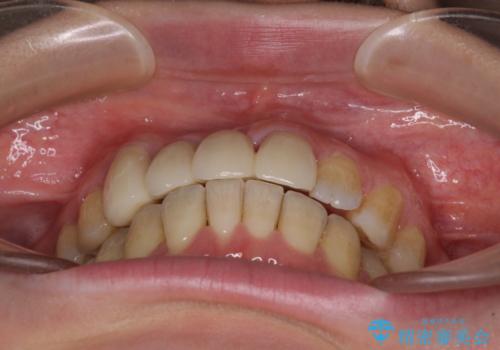

転んで前歯が欠けた 折れた前歯をきっかけに矯正治療で歯列をきれいに整える

- 転倒により前歯の一部が欠けてしまったとのことで来院された患者様です。

神経が保存できる歯、神経を除去しなければならない歯、抜歯が必要な歯があり、ブリッジやインプラントなどによる治療を提案しました。

元々歯並びが気になっていたとのことで、前歯の治療を行うことを契機に矯正治療も行うこととしました。

本来であれば積極的に小臼歯を抜歯して口元を下げても良いのですが、前歯を1本抜歯しないといけなくなったため、非抜歯矯正をインビザラインを用いて行うこととしました。